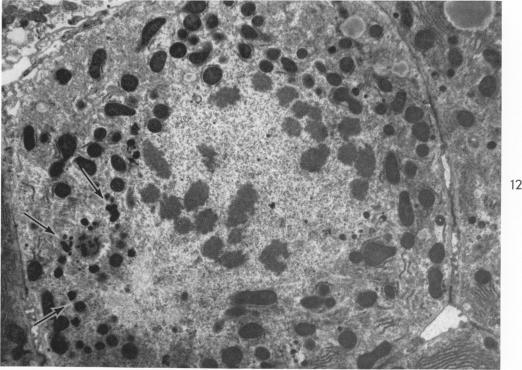

The Movement of Iron-Laden Lysosomes in Rat Liver Cells During Mitosis.

Am J Pathol. 1965 May;46(5):803-27.